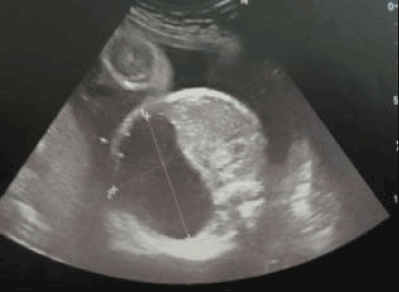

A 3.2 kg full-term female, aged of 2 months with no familial history, was hospitalised in our paediatric surgery department for exploration of two intra-peritoneal cystic malformations. She was a product of a normal vaginal delivery with APGAR 9/10. Parents were not consanguineous. Antenatal ultrasonography (28 WG) showed two anechoic cystic malformations (1.7x4.5 cm), which seemed to be dependent on the left kidney (Figure 2). A preliminary diagnosis of a polycystic kidney disease, a digestive duplication, a Cystic lymphangioma and pancreatic cyst was made.